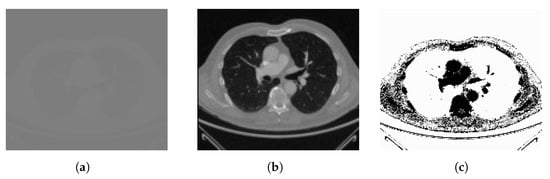

The effectiveness of these preprocessing measures can be visually appreciated in Figure 6, which demonstrates the results of histogram equalization (HE) applied to lung CT scan and chest X-ray images, along with their corresponding histogram distributions. This rigorous preprocessing lays the foundation for achieving consistent and high-quality results in the subsequent medical image segmentation processes, ultimately enhancing the accuracy and reliability of healthcare applications.

Figure 6.

Histogram equalization (HE) preprocessing for lung CT scan and chest X-ray images demonstrating the resulting histogram distributions. Grayscaling 8-bit images of (a) lung CT scan and (c) chest X-ray images followed by HE preprocessing in (b) and (d), respectively, with histograms illustrating the outcome in each case.

Figure 6 highlights significant improvements in image clarity after preprocessing, which are particularly evident in the comparison between Figure 6a,c. Histogram analysis reveals varying distributions in Figure 6a,b, but preprocessing (Figure 6c,d) achieves a uniform distribution through histogram equalization, which enhances overall visual quality and preserves critical details. Our model processing, employing histogram equalization, effectively enhances image clarity and visual quality, which contributes to a more precise depiction of features.